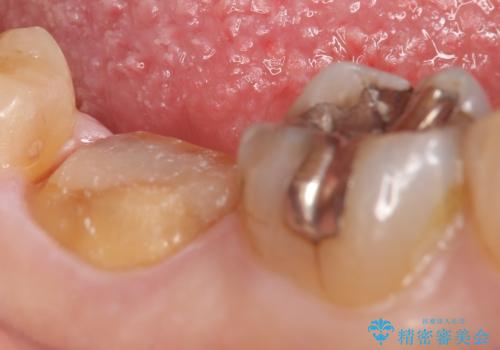

古い樹脂やカリエスを除去後、形を整え、オールセラミッククラウンによる補綴を行いました。

今回用いたオールセラミッククラウンはジルコニアフレームという白い素材の上にセラミックを盛っているため、審美性が非常に高いのが特徴です。

また、ジルコニアは人工ダイヤモンドの材料にも使われているほど高い強度を持っており、そのためオールセラミッククラウンは審美性だけでなく、奥歯やブリッジの補綴も可能とするクラウンです。